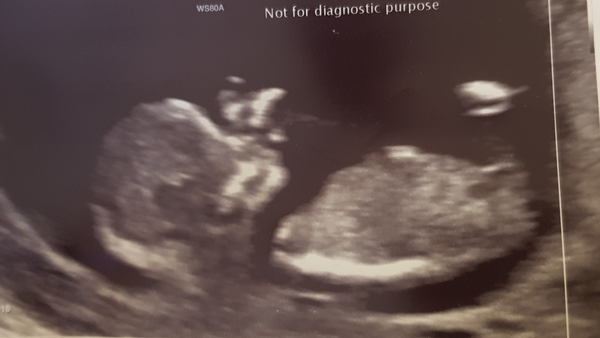

Had my scan today.....thankfully we got to see a wriggly bean waving at us!! Finally starting to seem real....it's been 11 years since I last did this!!

@dolleymix New EDD 10th August

ScotsBaby2 · 30/01/2019 21:19

@Dolleymix looks like baby is sleepy rubbing their wee eyes.